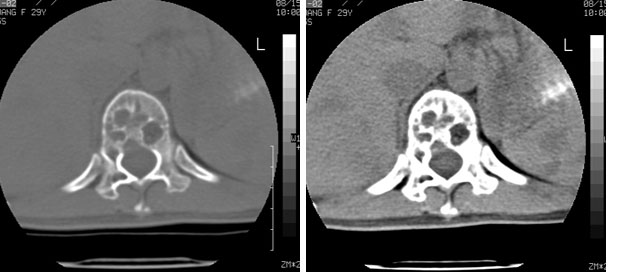

标题: CT10087:女,29岁,多发肿瘤样病变。 [打印本页]

标题: CT10087:女,29岁,多发肿瘤样病变。

车祸致t12压缩性骨折,行ct扫描意外发现椎体多发肿瘤样病变,建议加拍骨盆平片,患者平常无症状。

椎体多发性溶骨性破坏,部分融合,椎旁无软组织肿块、椎间隙正常,t12 压缩,脾脏增大,其内示多发低密度影,首先考虑多发性骨髓瘤。病人较年轻,平素无异常,转移瘤可能性小。